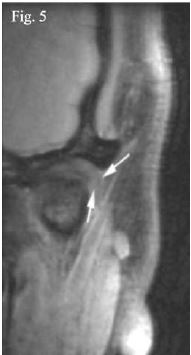

Además, debe tenerse en consideración que hasta hoy la mayoría de los resonadores utilizados son de 1.5 tesla mientras que aquellos de mayor potencia de campo magnético brindan imágenes con mayor precisión diagnóstica41. Por eso, creemos que varios artículos no han logrado diferenciar estas estructuras por los factores inherentes del equipo resonador. Para graficar esto, en la imagen (figura 5) presentada por Orhan et al., en el año 2005 se puede ver claramente lo imposible que resulta diferenciar el disco de la cápsula articular42. A medida que la tecnología va evolucionando, autores como Wang, Yang y Yu en el año 2009 ya mencionan su visualización en T1 y con una densidad muy similar a la del disco articular particularmente cuando se observa en la reformación coronaria17. Luego ya para el año 2015 Hagenkord y Basel presentaron imágenes de la cápsula articular donde la definieron con una densidad similar a la de la cápsula, como fue comentado anteriormente ya que están conformadas por el mismo tejido43; así, con una imagen de archivo queremos demostrar que la imagen del disco articular puede ser diferenciada de la cápsula articular (figura 6).